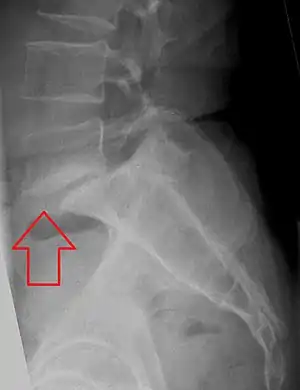

| X-ray of the lateral lumbar spine with a grade III anterolisthesis at the L5-S1 level | |